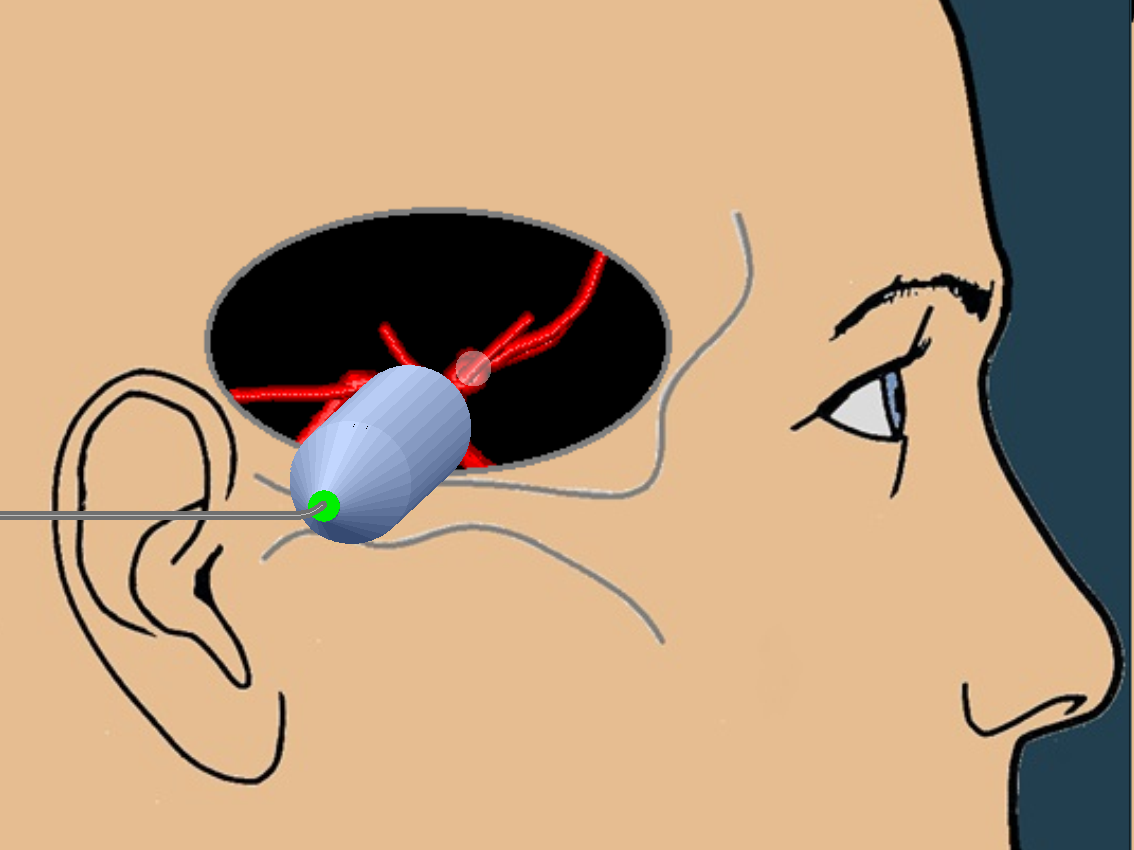

The Basics

B-Mode Anatomy